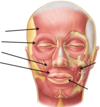

Label the somatic sensory innervation to the head

Label the diagram of facial nerve course

Label the facial nerve diagram

Label and detail the muscles of facial expression